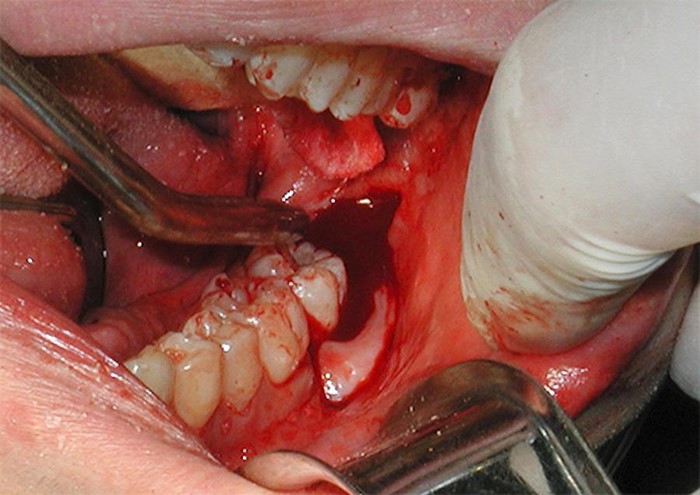

Nhổ răng khôn là thủ thuật khó, chiếc răng khôn mọc lệch, mọc kẹt, mọc ngầm trong xương hàm sẽ không thể lấy ra nếu bác sỹ không có kinh nghiệm và kỹ năng, ngoài ra các dụng cụ nhổ răng đa dạng cho các tình huống phát sinh cũng vô cùng cần thiết. Dụng cụ nhổ răng ví như thanh gươm trong tay hiệp sĩ vậy, nếu không có thanh gươm sắc bén thì dù giỏi đến đâu cũng khó cho kết quả tốt.

Tiểu phẫu nhổ răng khôn là chỉ định thường xuyên xảy ra giúp loại bỏ những phiền toái mà răng khôn đem lại như đau nhức, mắc thức ăn, sâu hỏng răng bên cạnh, hôi miệng, sưng đau… Vậy tiểu phẫu nhổ bỏ răng khôn có thực sự cần thiết bài viết dưới đây chúng tôi sẽ giải đáp cho các bạn hiểu rõ hơn.

Thủ thuật nhổ răng khôn nhất là đối với răng khôn mọc lệch thường gặp nhiều biến chứng hơn nhổ răng bình thường. Tại sao lại như vậy và làm thế nào để chọn được nha khoa uy tín để có cuộc nhổ răng an toàn.